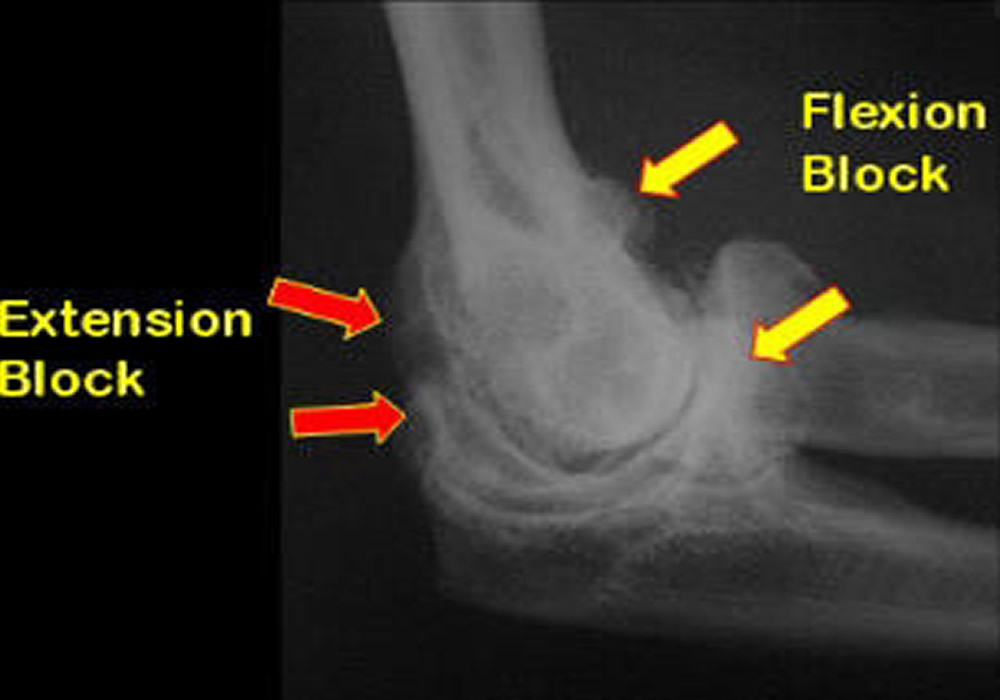

Διάγνωση

Η εκτίμηση γίνεται από τον ορθοπεδικό και μπορεί να περιλαμβάνει:

• Κλινική εξέταση για τον έλεγχο της κίνησης

• Ακτινογραφίες ή μαγνητική τομογραφία για ανίχνευση βλαβών ή εμποδίων στην άρθρωση

• Αρθροσκόπηση ή ανοικτό χειρουργείο για αφαίρεση ουλώδους ιστού ή οστικών εμποδίων